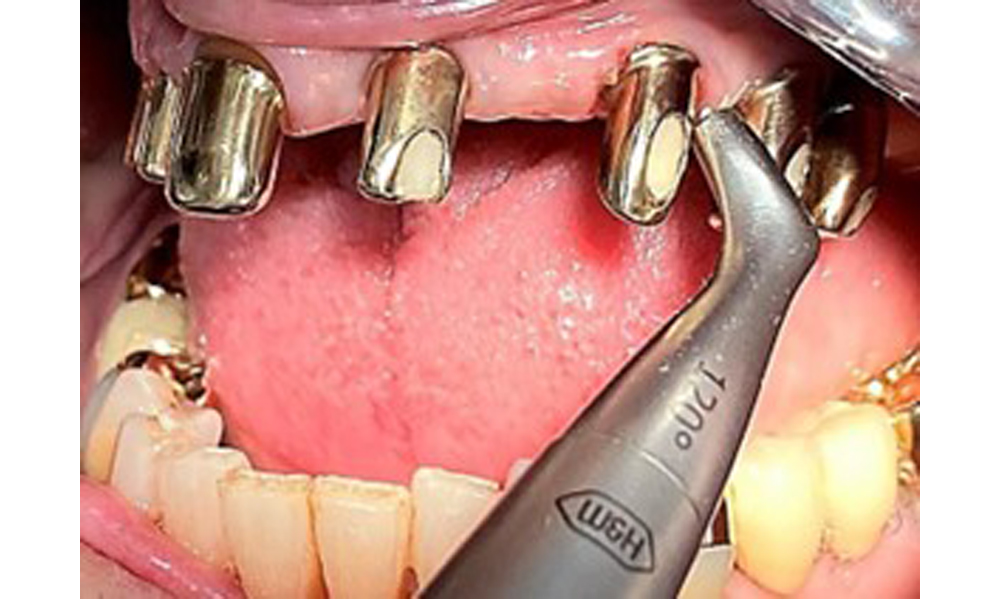

The dental findings are as follows: Combined removable implant and tooth-supported telescopic prostheses on implants 15, 13, 21, 23, 24, 25 and tooth 11 (Fig. 1, Fig. 2, Fig. 3). The patient was fitted with a fixed mandibular denture. Adequate bridges were present over 37 to 34 and 45 to 47 (Fig. 4), the crown margins were intact and there were no active caries. A composite filling with a marginal gap was present on tooth 43. There was mandibular gingival recession, exposing 1 to 3 mm of root surface. This also applies to 11.

Occlusal view of the mandible.

Fig. 4: Occlusal view of the mandible.